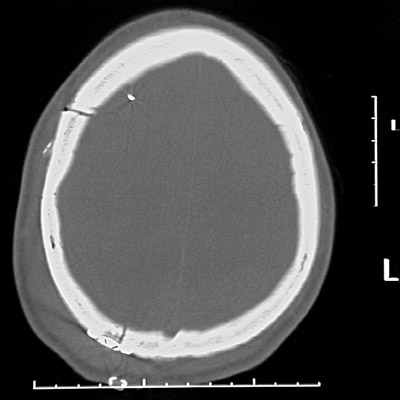

| This head CT scan in "bone window" demonstrates a skull fractures on the right with diastasis of the sutures. However, this is not a depressed skull fracture. There is marked overlying soft tissue swelling in the scalp, and a small laceration has been closed with staples. In the view below following craniotomy for removal of an epidural hematoma, the swelling has diminished and the posterior fracture has been stabilized with a short metal plate. |